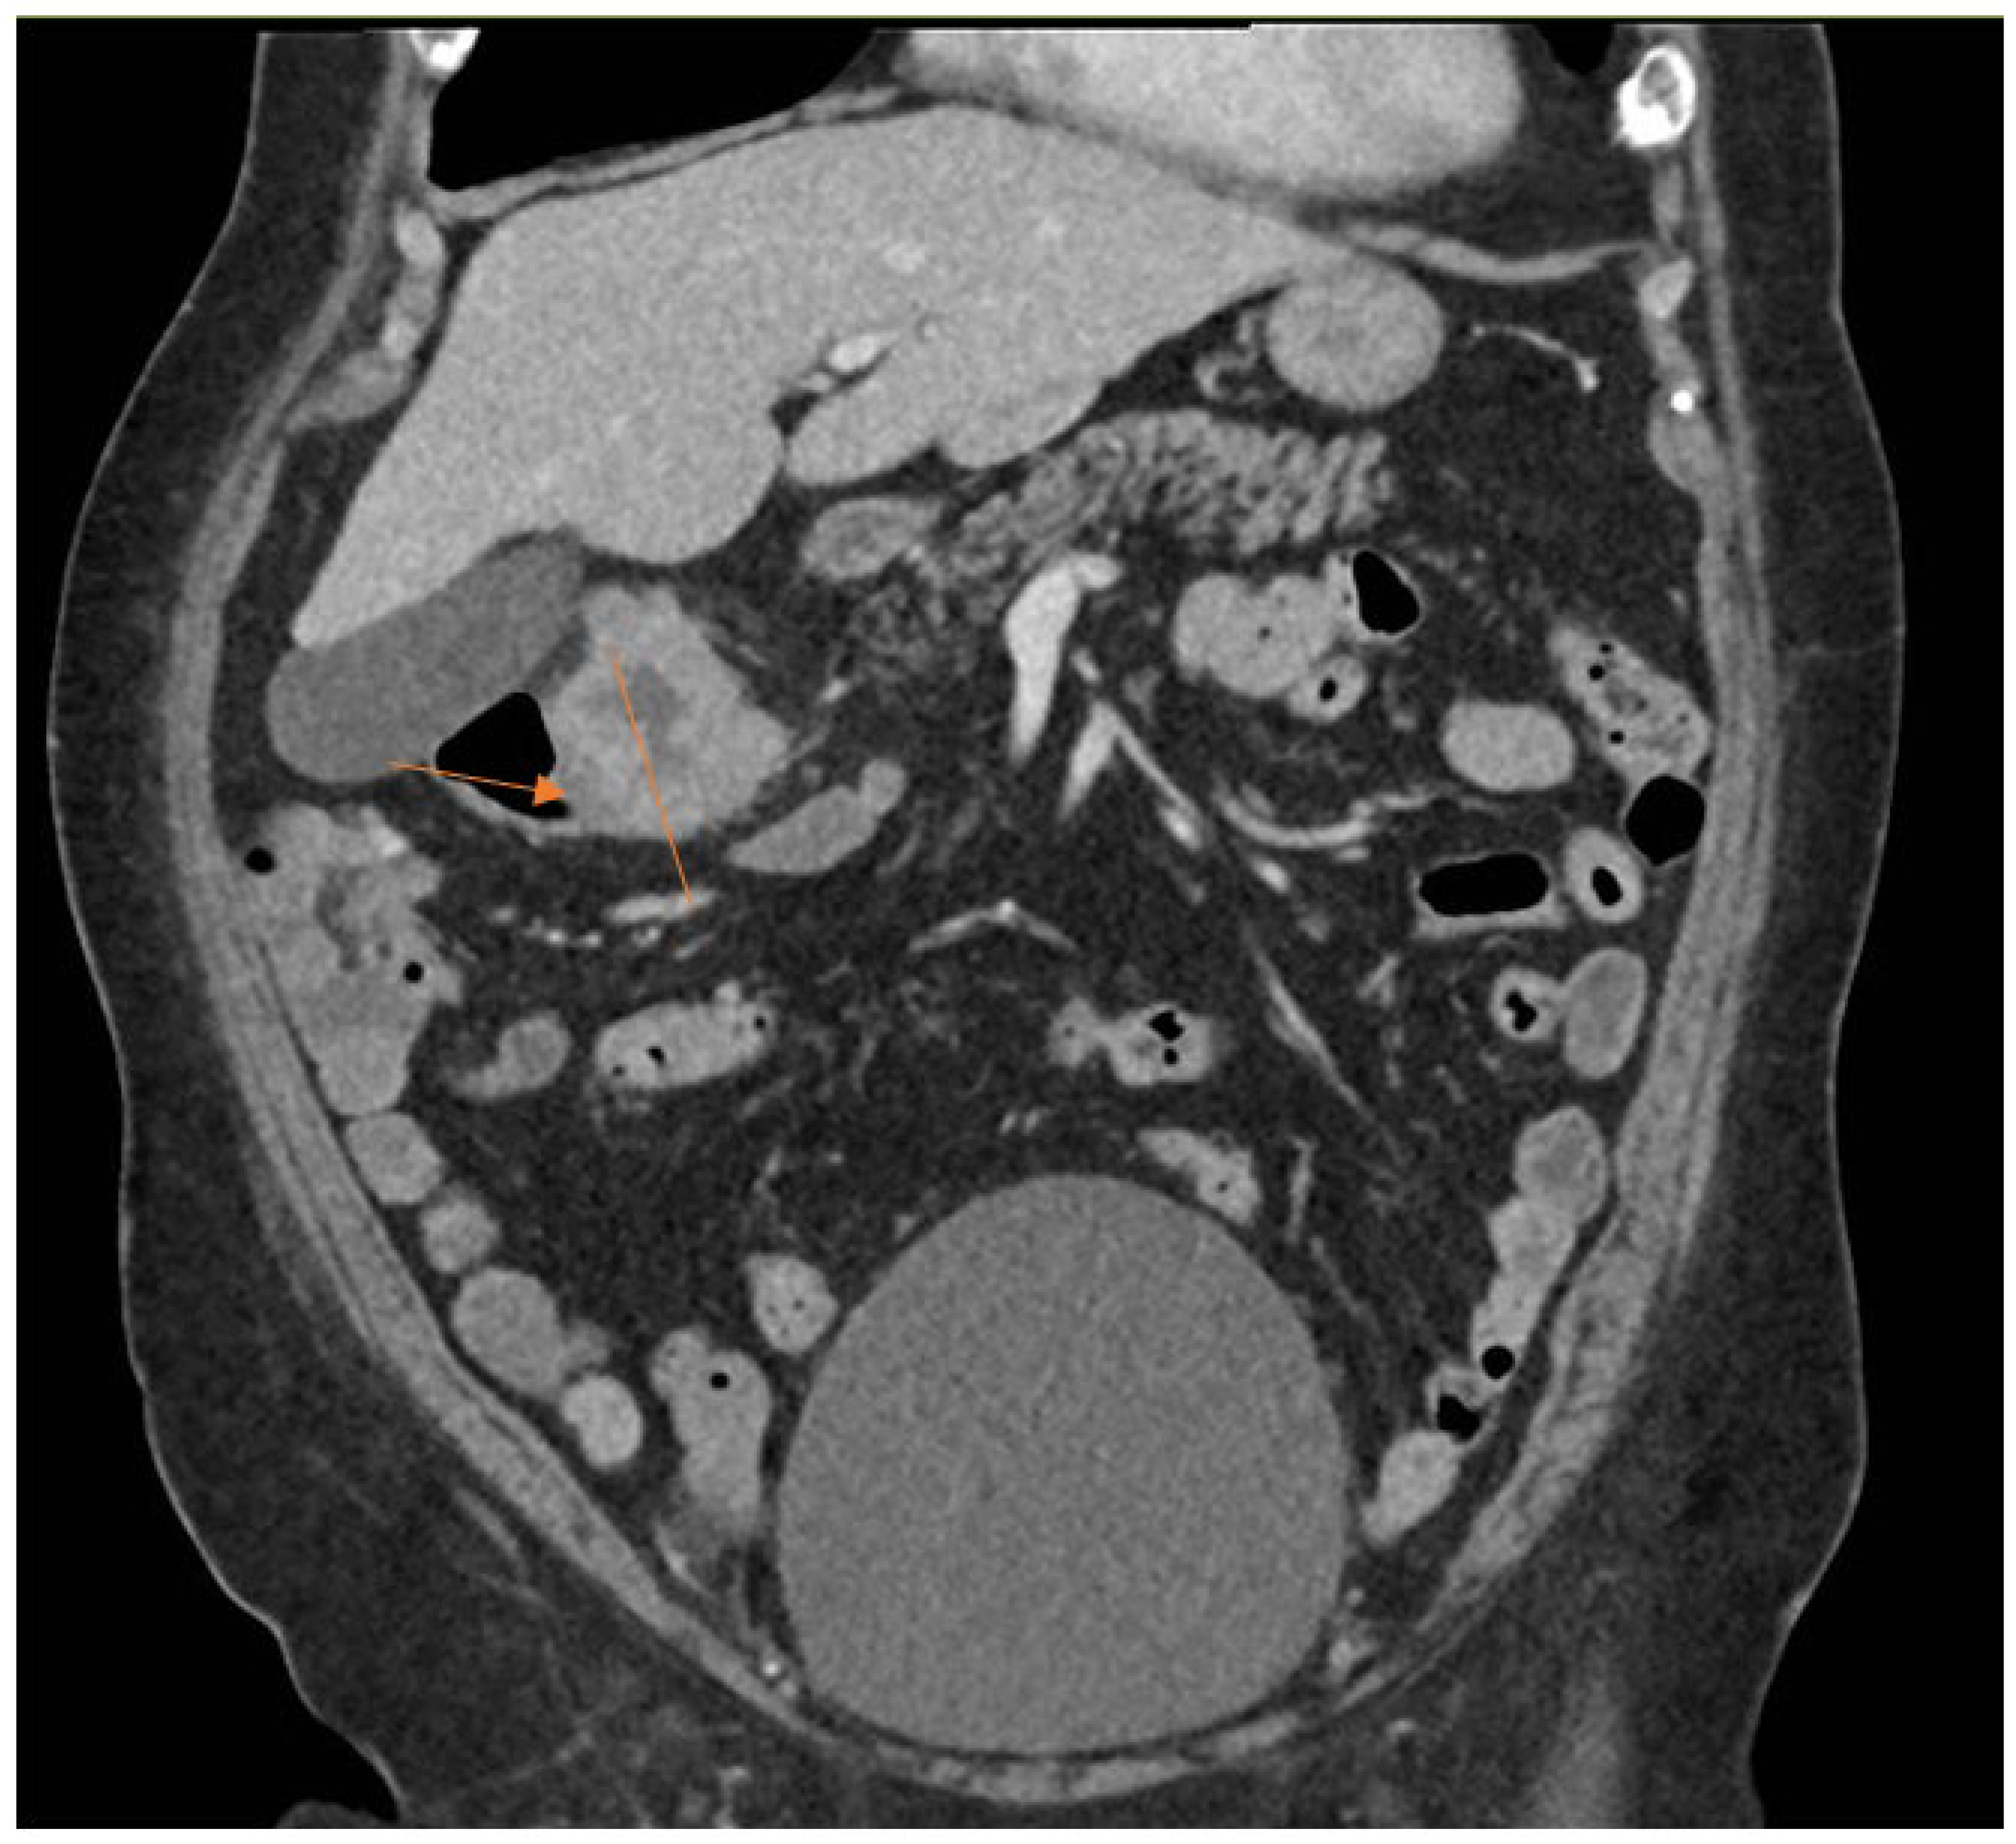

The clinical characteristics of the three cases are summarized in Table 1. The laboratory characteristics of the three cases are summarized in Table 2. All three cases in our study presented with knee pain and swelling at least after five years from the primary total knee arthroplasty. Two out of three cases underwent single-stage revision surgery, whereas one case underwent the DAIR procedure. Laboratory markers indicative of acute inflammatory processes such as CRP and ESR were raised markedly in all three cases. The CT-AP scan performed in Patient 1 showed a colorectal mass, as seen in Figure 1 and Figure 2.

She underwent a single-stage revision surgery. Intraoperative findings revealed copious purulent fluid; and intraoperative cultures confirmed B. fragilis. Postoperative CT-AP revealed a suspicious transverse colon mass. Subsequent colonoscopy confirmed a large proximal transverse colon tumour. Diagnosis of colorectal carcinoma was confirmed with histology showing adenocarcinoma. Computed tomography of the thorax demonstrated incidental pulmonary emboli, and anticoagulation therapy was initiated. She was discharged on long-term intravenous antibiotics and scheduled for definitive colorectal surgery after completing anticoagulation. The patient underwent a total of three months duration of antibiotics, consisting of six weeks of intravenous amoxicillin-clavulanic acid and six weeks of oral metronidazole.

Figure 2. Coronal cut of CT-AP scan showing colorectal carcinoma as indicated by arrow.